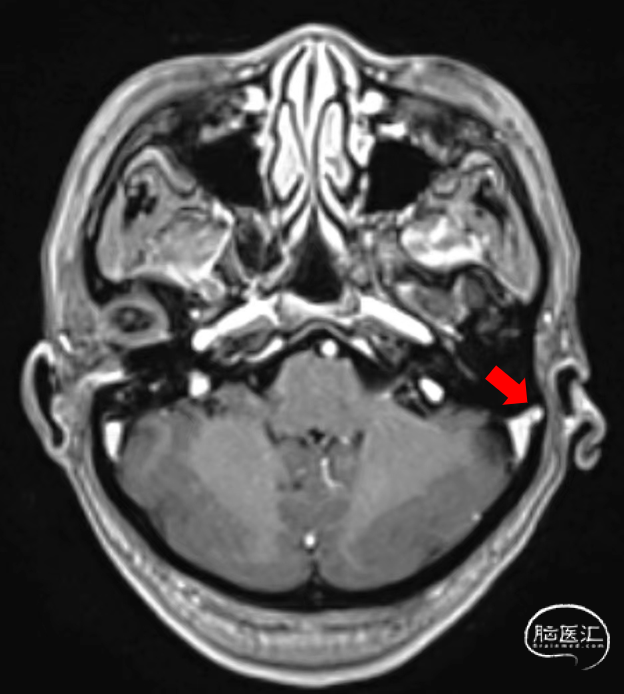

➤MR

红色箭头示静脉窦憩室